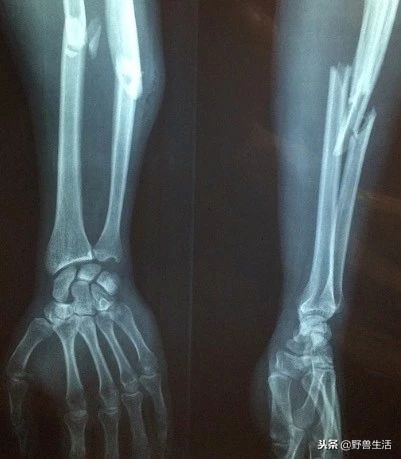

可别小看骨质疏松。骨质疏松和暴雨天的堤坝一样,大部分时间觉得没事,但是 一旦意外发生,比如说骨折——就已经太迟了。

最可怕的还不是摔一跤就能把腿摔断,而可能只是打了个喷嚏,骨质疏松就会让腰椎的某个环节就此折断,带来压缩性骨折,身高瞬间就下降了 1cm。